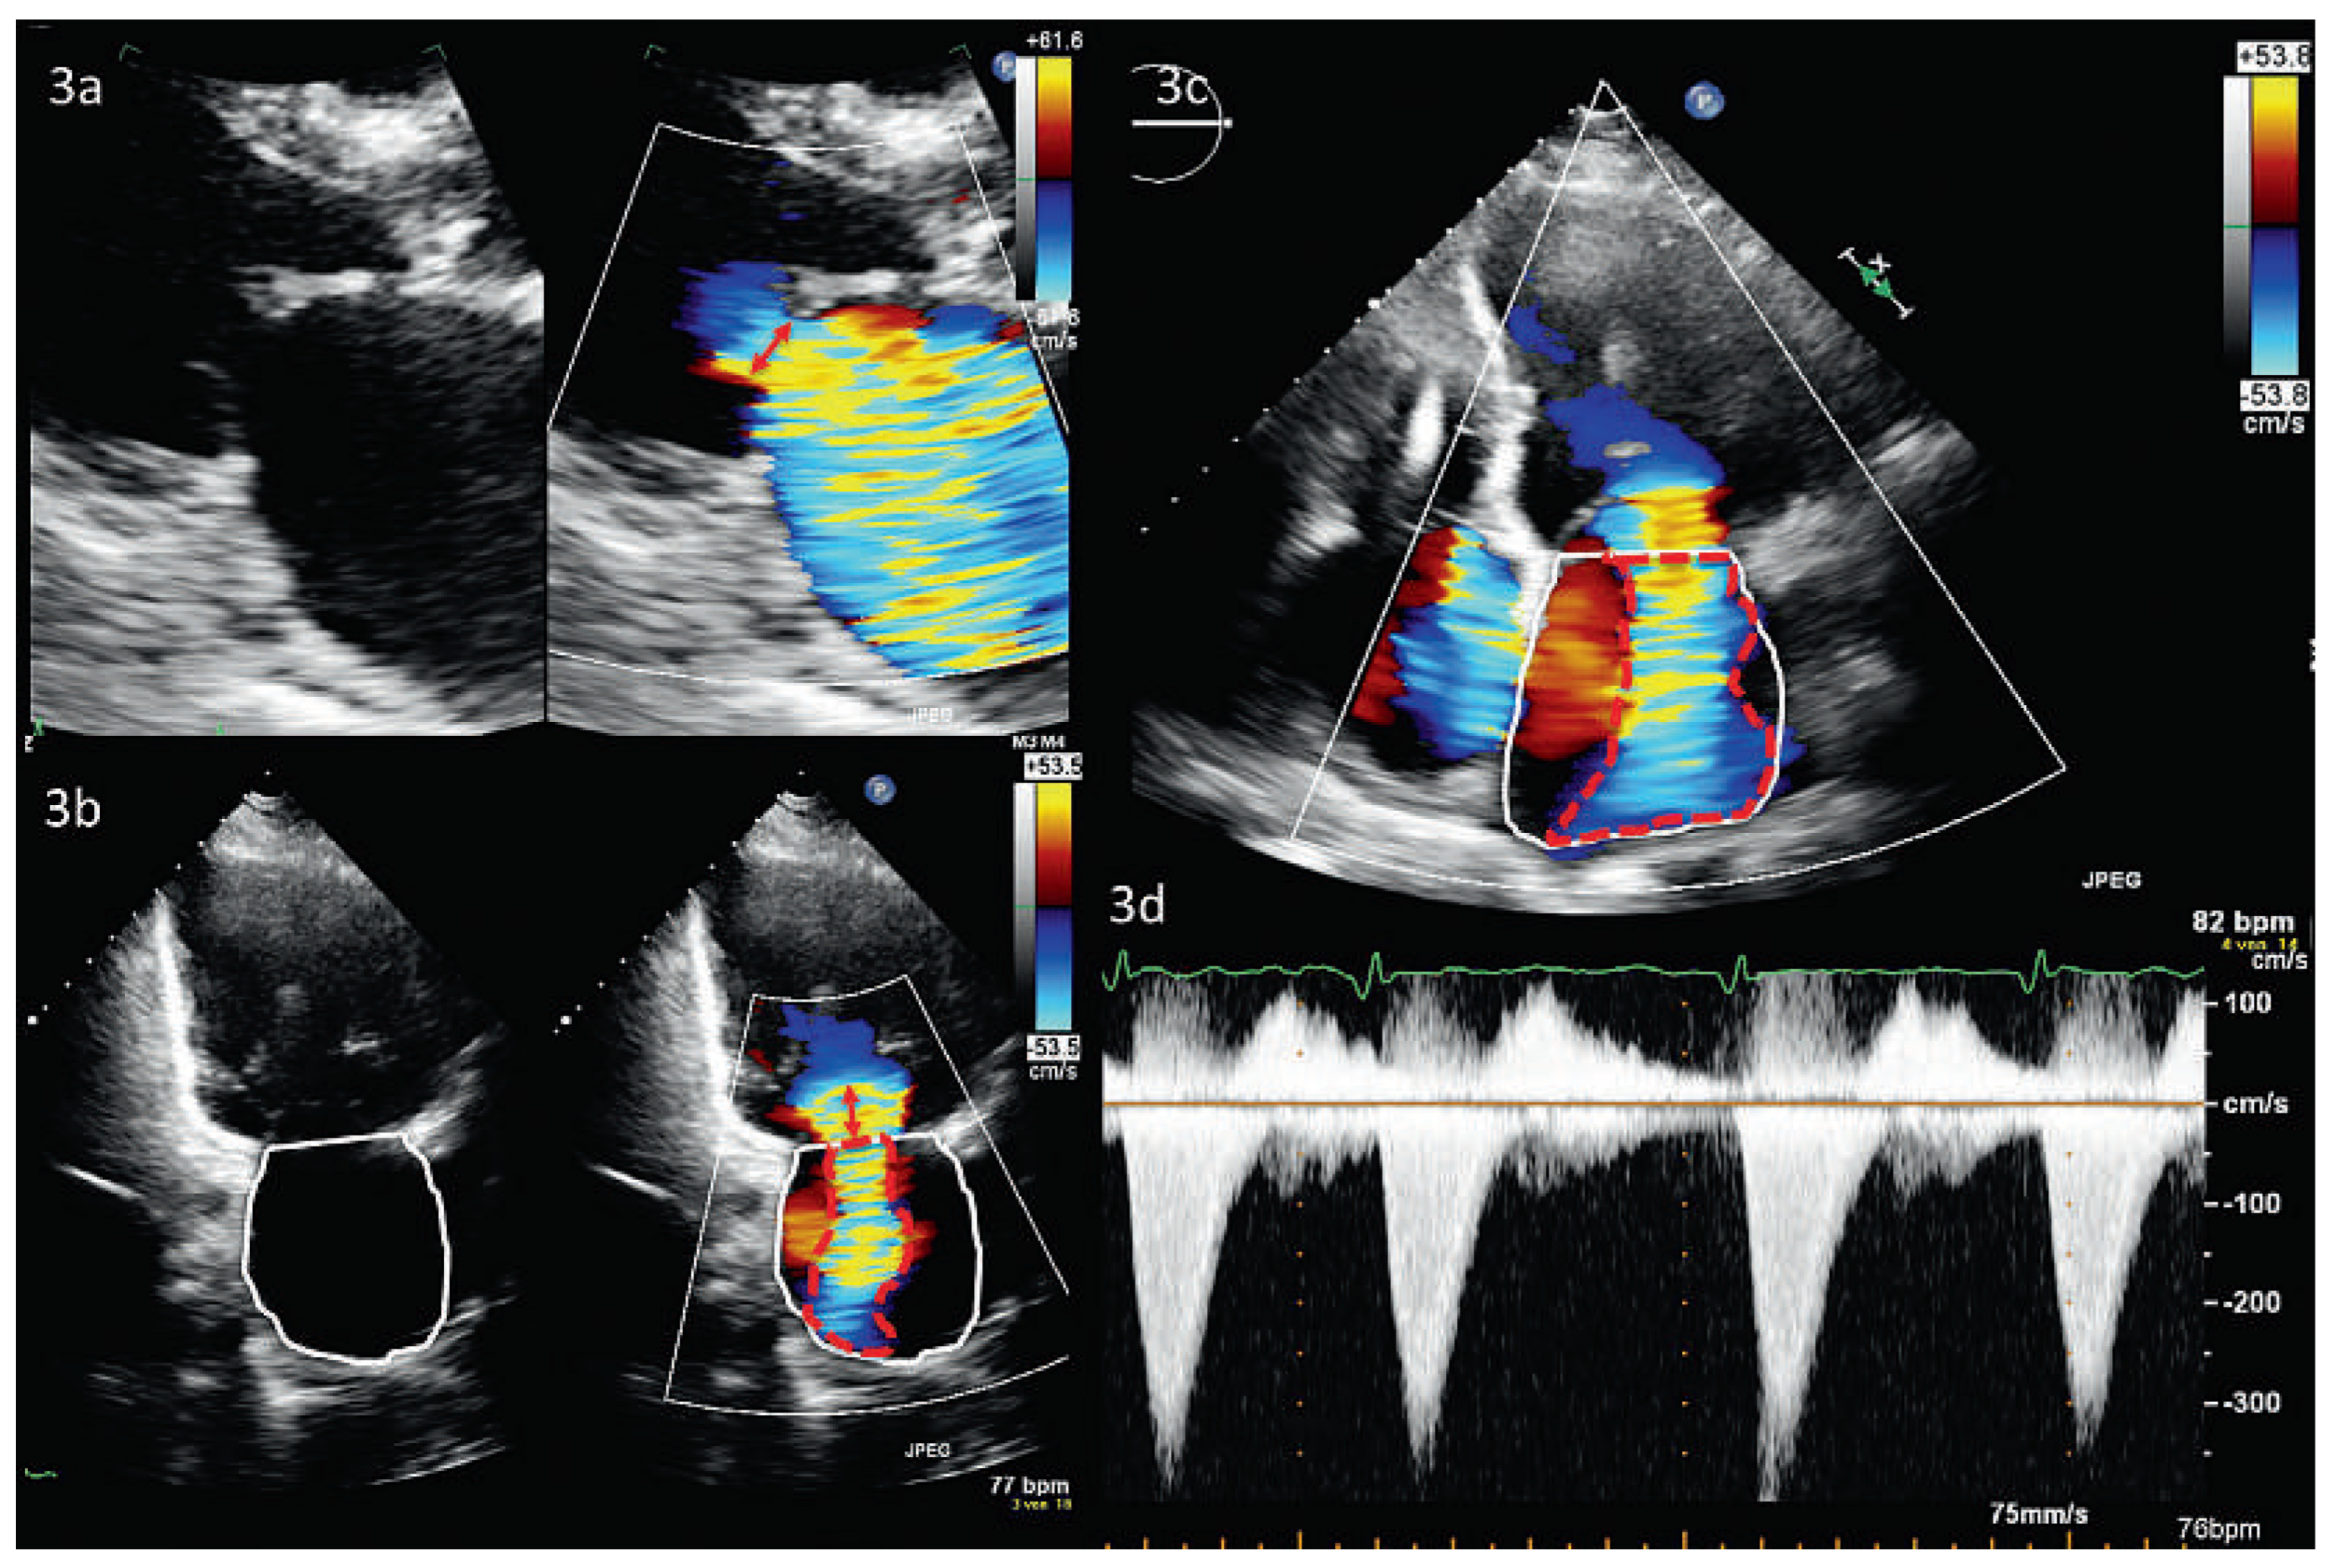

Abbildung 12. Papilläres Fibroelastom, Vergleich CT, 2D-TEE, 3D-TEE (gleiche Patientin). 12a: das Fibrolastom lässt sich im CT wegen ungenügender zeitlicher Auflösung nicht darstellen. 12b und c: kleines Fibroelastom (histologisch gesichert) am posterioren Mitralklappensegel (roter Stern). Abkürzungen: PML, posteriores Mitralklappensegel; Ao, Aortenwurzel.

Wenn ausgeprägte Verkalkungen das Bild der gemischten Mitralinsuffizienz beherrschen, so kann die Qualität der transthorakalen Echokardiographie massgebend beeinträchtigt sein. Das kann bis hin zur völligen Verkennung einer Mitralinsuffizienz im Schallschatten des verkalkten Anulus reichen. Hier ist bei klinischer Symptomatik eine transesophageale Echokardiographie, ggf. auch eine CM- Roder CT-Untersuchung zu erwägen (Abbildung 11). Speziell die CT ist eine hervorragende Modalität zur Darstellung der Verkalkungen, die exakte Lokalisation der Verkalkung hilft bei der operativen Planung (Resektion bzw. Rekonstruktion des Anulus) [49]. Bei weniger ausgeprägten Veränderungen hingegen stellt die TTE oder TEE das subtile Zusammenspiel zwischen Kalk, Fibrose, Segelverdickung und -beweglichkeit oft sehr genau dar – eine notwendige Voraussetzung, um die exakte Regurgitationsursache zu definieren und eine geeignete Therapie abzuleiten. Die geringe zeitliche Auflösung limitiert hier insbesondere den Einsatz der CT. Die vor allem diastolisch aufgenommenen Bilder können dazu führen, dass ein Mitralklappenprolaps übersehen wird. Infolge der geringen zeitlichen Auflösung können zudem Verdickungen oder Tumore als Ursache einer Mitralinsuffizienz in der CT verpasst werden (Abbildung 12).